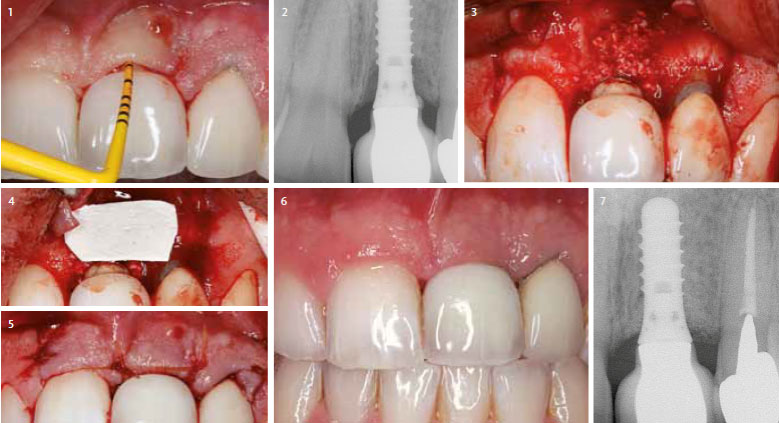

Regenerative or resective therapy (Supportive therapy protocol D)

Only if infection is controlled successfully, it is reasonable to discuss treatment approaches to either restore the bony support of the implant by means of regenerative techniques or to reshape the periimplant soft tissues and/or bony architecture by means of resective surgical techniques, depending on esthetic considerations and morphological characteristics of the lesion.

So far, evidence that bone fill of periimplant defects resulting from previous periimplantitis may be achieved following anti-infective therapy and using the biological principle of guided tissue regeneration (GTR) (FIG.4,5,6,7) However, the re-osseointegration of a previously contaminated implant surface into regenerated bone has not yet been demonstrated histologically. Treatment with the combination of grafts and e-PTFE membranes may lead to bone fill and improved soft tissue conditions. Comparison of the overall outcomes of cases treated with grafts alone, e-PTFE membranes alone, or their combination – does not indicate a superiority to the combination.